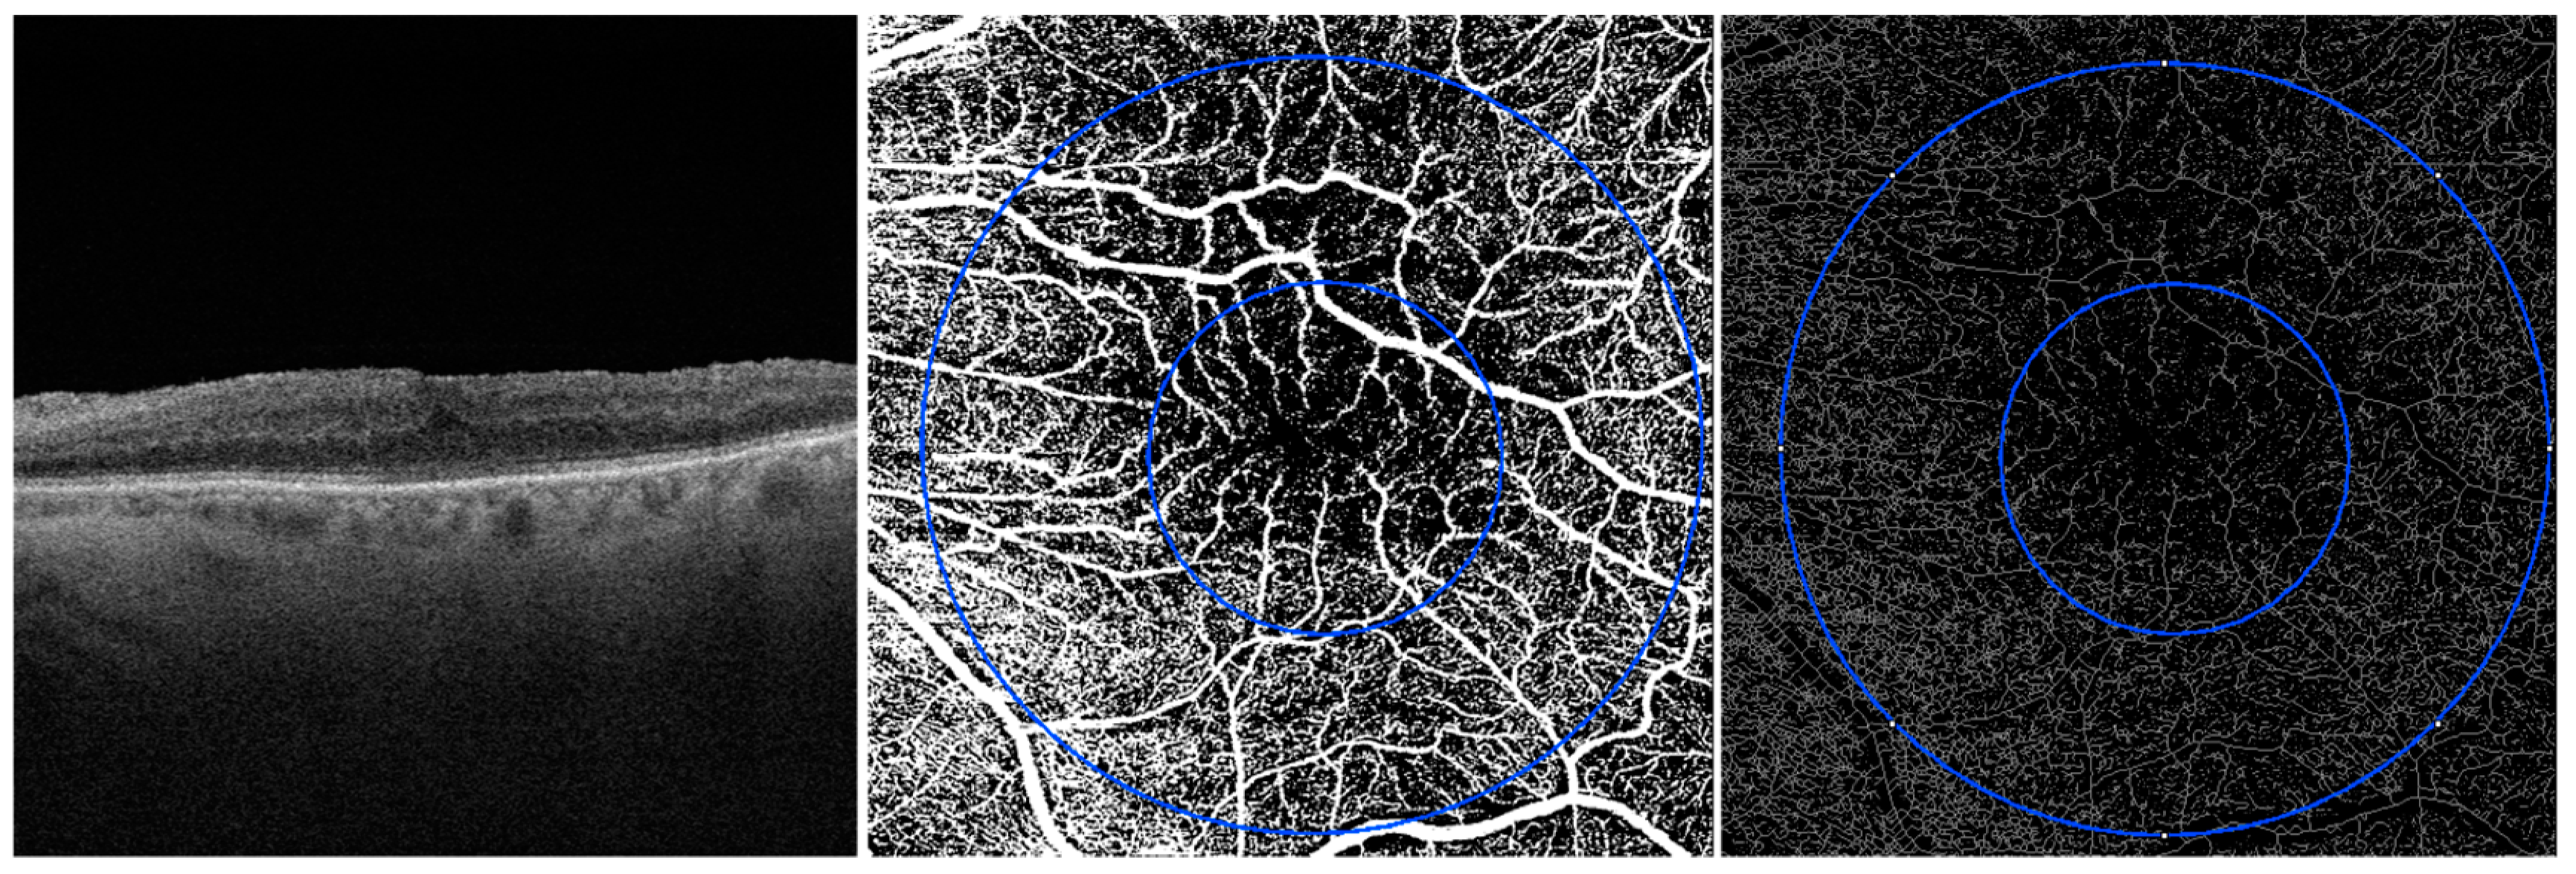

2.2. Image Acquisition

2.3. Image Processing